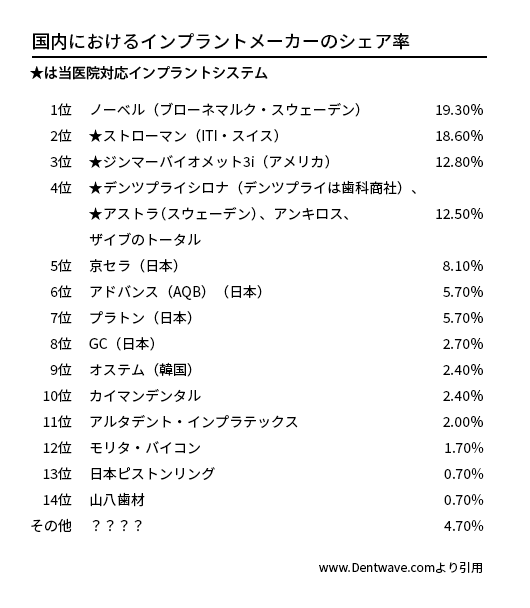

200社を超える世界のインプラントメーカー

現在、世界には200社を超えるインプラントメーカーが存在し、日本へは厚生労働省認可としては約30社のものが認められています。それ以外は歯科医の個人責任による個人輸入です。正直、よく分からない某国メーカーや、いつのまにか撤退、倒産、消滅していて、アフターケアが不可能になるものや、中には劣悪な製品ゆえの長期安定性に欠けるものも存在します。世界的な知名度、シェアを有していても日本では無名であるものや、逆に日本では知名度、シェア有していても世界的には無名なものもあり、一概には判断できません。中には無茶苦茶なディスカウントを行うメーカーや、安価をうたいつつもメーカー自体非常に怪しいものなど、販売方法に疑問があるメーカーも存在します。また、メーカー自体が倒産してしまったものもありますが、このような場合、消耗品パーツの供給などアフターケアに問題が出ています。

インプラント治療を行おうとお考えの場合、歯科医院がどのようなインプラントシステムを使用しているかご確認された方が良いでしょう。もっとも「ブランドインプラント」を使用することにより、患者さんにアピールしている場合もありますので注意が必要です。あくまでも使う側、歯科医の知識、スキル、経験が大事です。